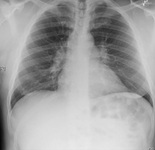

Chest x-ray in a patient with bronchogenic carcinoma showing a left-sided pleural effusion

From: R. Thakkar, Student BMJ. 2001;9:458